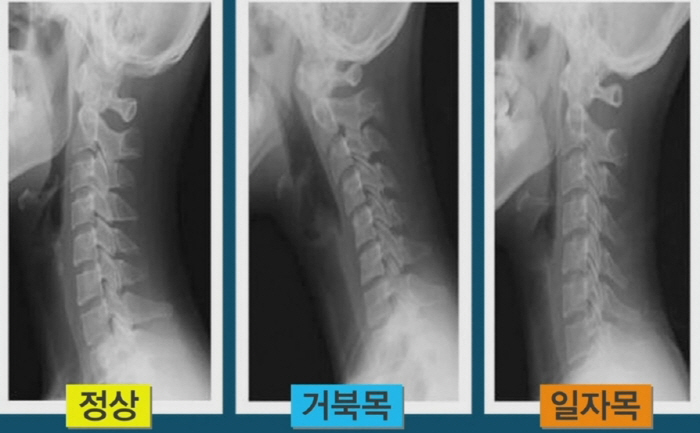

사람의 목뼈는 7개로 이러져있는데 이사이에는 충격을 흡수하여 주는 연골조직 추 갑판이라는 것이 있습니다. 이곳에 신경 압박을 가해지면 경추 추간판 탈출증이라고 하는데 이게 목디스크입니다. 문제가 생기는 이유는 퇴행성 변화로 인해 나타납니다.